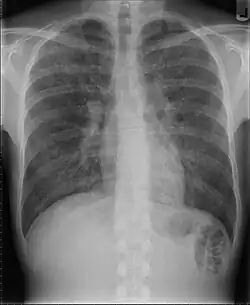

Pneumocystis jirovecii, voorheen ook Pneumocystis carinii genaamd, is een gist en genoemd naar de Tsjechische onderzoeker Otto Jírovec.[2] Deze kan verantwoordelijk zijn voor het ontstaan van longontstekingen bij immuungecompromitteerde patiënten, zoals hiv-patiënten of gebruikers van immunosuppressiva. Deze soort longontsteking was vroeger bekend als Pneumocystis carinii-pneumonie (PCP). Omdat de afkorting al ingeburgerd was in de medische wereld, werd de afkorting na de naamsverandering behouden en wordt de ziekte nu Pneumocystis jirovecii-pneumonie genoemd.